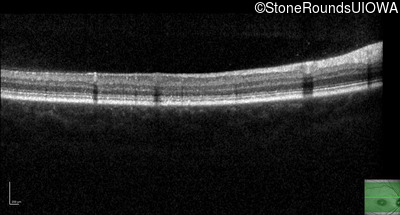

Optical Coherence Tomography - Right - 20/125 sc

Exemplar / OCT Stack